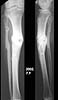

I am a 55-year-old male who suffered a compound fracture of the right tibia and fibula and extensive soft tissue damage, including vascular damage, from the impact of an automobile pinning the leg to a concrete wall in 1971. This occurred while I was a pedestrian. Emergency surgery restored circulation and set the tibia and fibula fragments with no internal fixation (due to concern about infection) and plaster cast immobilization. Later a bone graft was performed, and after physical therapy an apparently full recovery occurred, except a slight varus deformity, reduced vascularity, and reduced range of motion in the ankle. Over the years, the varus deformity worsened to 22 degrees and led to moderate osteoarthritis. To correct the deformity and straighten the tibia, an open-wedge osteotomy was performed in November 1999, with a bone graft from the other iliac crest. Plate fixation was used, as the bone was too hard to ream, so it was impossible to insert a pin. I have used the Exogen ultra-sound device every day since the surgery. Gradual improvement led to enhanced weight-bearing ability, and I have been walking with a cane since April 2000. Although X-rays taken June 16 showed no deformity, the varus deformity has recurred in the October 16 X-rays.

I am interested in why this happened and what to do about it. Is a second osteotomy indicated? If so, is there a medical consensus on whether bone marrow implants promote osteogenesis? What about other implants of natural, artificial or combination materials? Are there any methods of reaming calcified bone for the purpose of pin insertion? Are there other remedies? Has anyone on the list seen varus deformities of the tibia recurring after an osteotomy? Would the Ilizarov device give better results within a reasonable time, taking into account age and impaired vascularity? And what other options exist that would straighten this thing out once and for all? I have copies of the June and October X-rays which can be sent as e-mail attachments off-list, and will be glad to answer questions insofar as possible.

Xrays demonstrate that the medullary canal of the tibia has been obliterated in the vicinty of the fracture. It can be restored with sharp tipped intramedullary guide rods and end cutting reamers. This needs to be carefully done with fluoroscopic guidance.